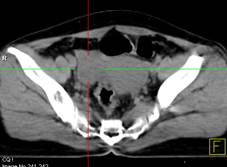

Hình 2. Bệnh nhân Lê Th. H., nữ, 58 tuổi, chẩn đoán: ung thư buồng trứng trái đã phẫu thuật và điều trị hóa chất năm 2011. Sau 8 tháng bệnh nhân kiểm tra thấy nồng độ chỉ điểm khối u CA 125 tăng cao (225ng/ml). Bệnh nhân được chỉ định chụp PET/CT kiểm tra. Trên hình PET/CT thấy tổn thương tái phát di căn màng bụng, trên hình CT không phát hiện được.